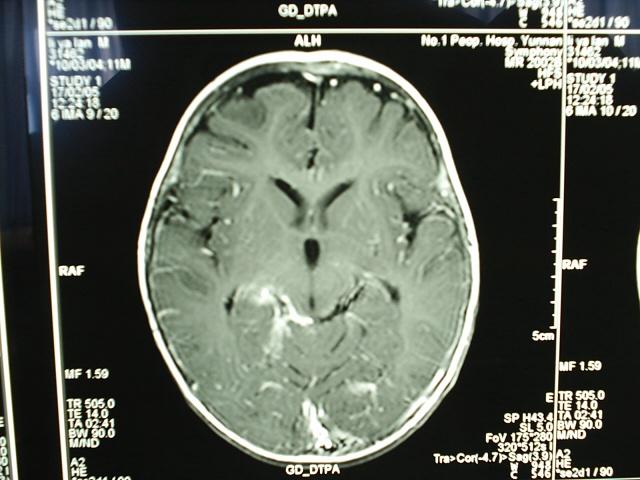

小儿结核性脑膜炎合并脱髓鞘改变MRI

病变部位在右侧大脑半球胼胝体压部强化部分。大家注意看